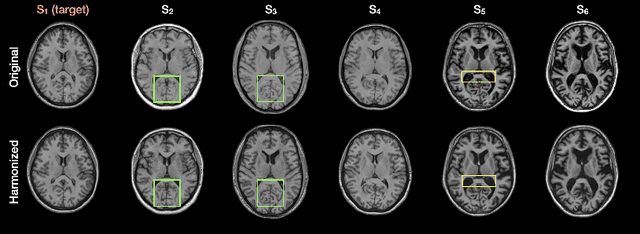

Abstract:The lack of standardization is a prominent issue in magnetic resonance (MR) imaging. This often causes undesired contrast variations due to differences in hardware and acquisition parameters. In recent years, MR harmonization using image synthesis with disentanglement has been proposed to compensate for the undesired contrast variations. Despite the success of existing methods, we argue that three major improvements can be made. First, most existing methods are built upon the assumption that multi-contrast MR images of the same subject share the same anatomy. This assumption is questionable since different MR contrasts are specialized to highlight different anatomical features. Second, these methods often require a fixed set of MR contrasts for training (e.g., both Tw-weighted and T2-weighted images must be available), which limits their applicability. Third, existing methods generally are sensitive to imaging artifacts. In this paper, we present a novel approach, Harmonization with Attention-based Contrast, Anatomy, and Artifact Awareness (HACA3), to address these three issues. We first propose an anatomy fusion module that enables HACA3 to respect the anatomical differences between MR contrasts. HACA3 is also robust to imaging artifacts and can be trained and applied to any set of MR contrasts. Experiments show that HACA3 achieves state-of-the-art performance under multiple image quality metrics. We also demonstrate the applicability of HACA3 on downstream tasks with diverse MR datasets acquired from 21 sites with different field strengths, scanner platforms, and acquisition protocols.